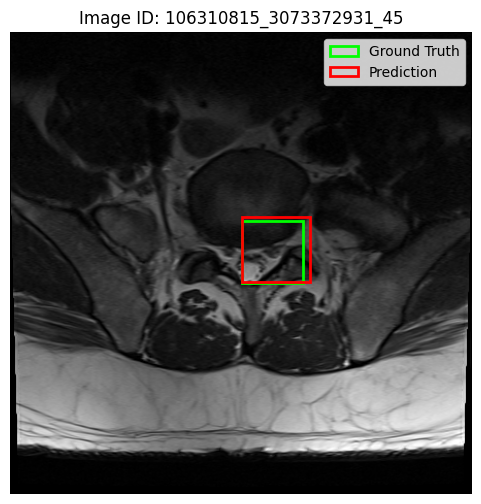

Prior to classification, we trained a 25-class Faster R-CNN model to localise spinal conditions at specific vertebral levels. Figure 6 presents qualitative results on three representative cases, showing predicted bounding boxes (red) and ground truth annotations (green). In the first two examples, the predicted bounding boxes are well-aligned with the ground truth, capturing the target regions with high spatial fidelity. The third image, however, reveals less overlapping predictions, reflecting reduced precision. These visualisations illustrate both the strengths and limitations of the detection module in complex anatomical contexts.